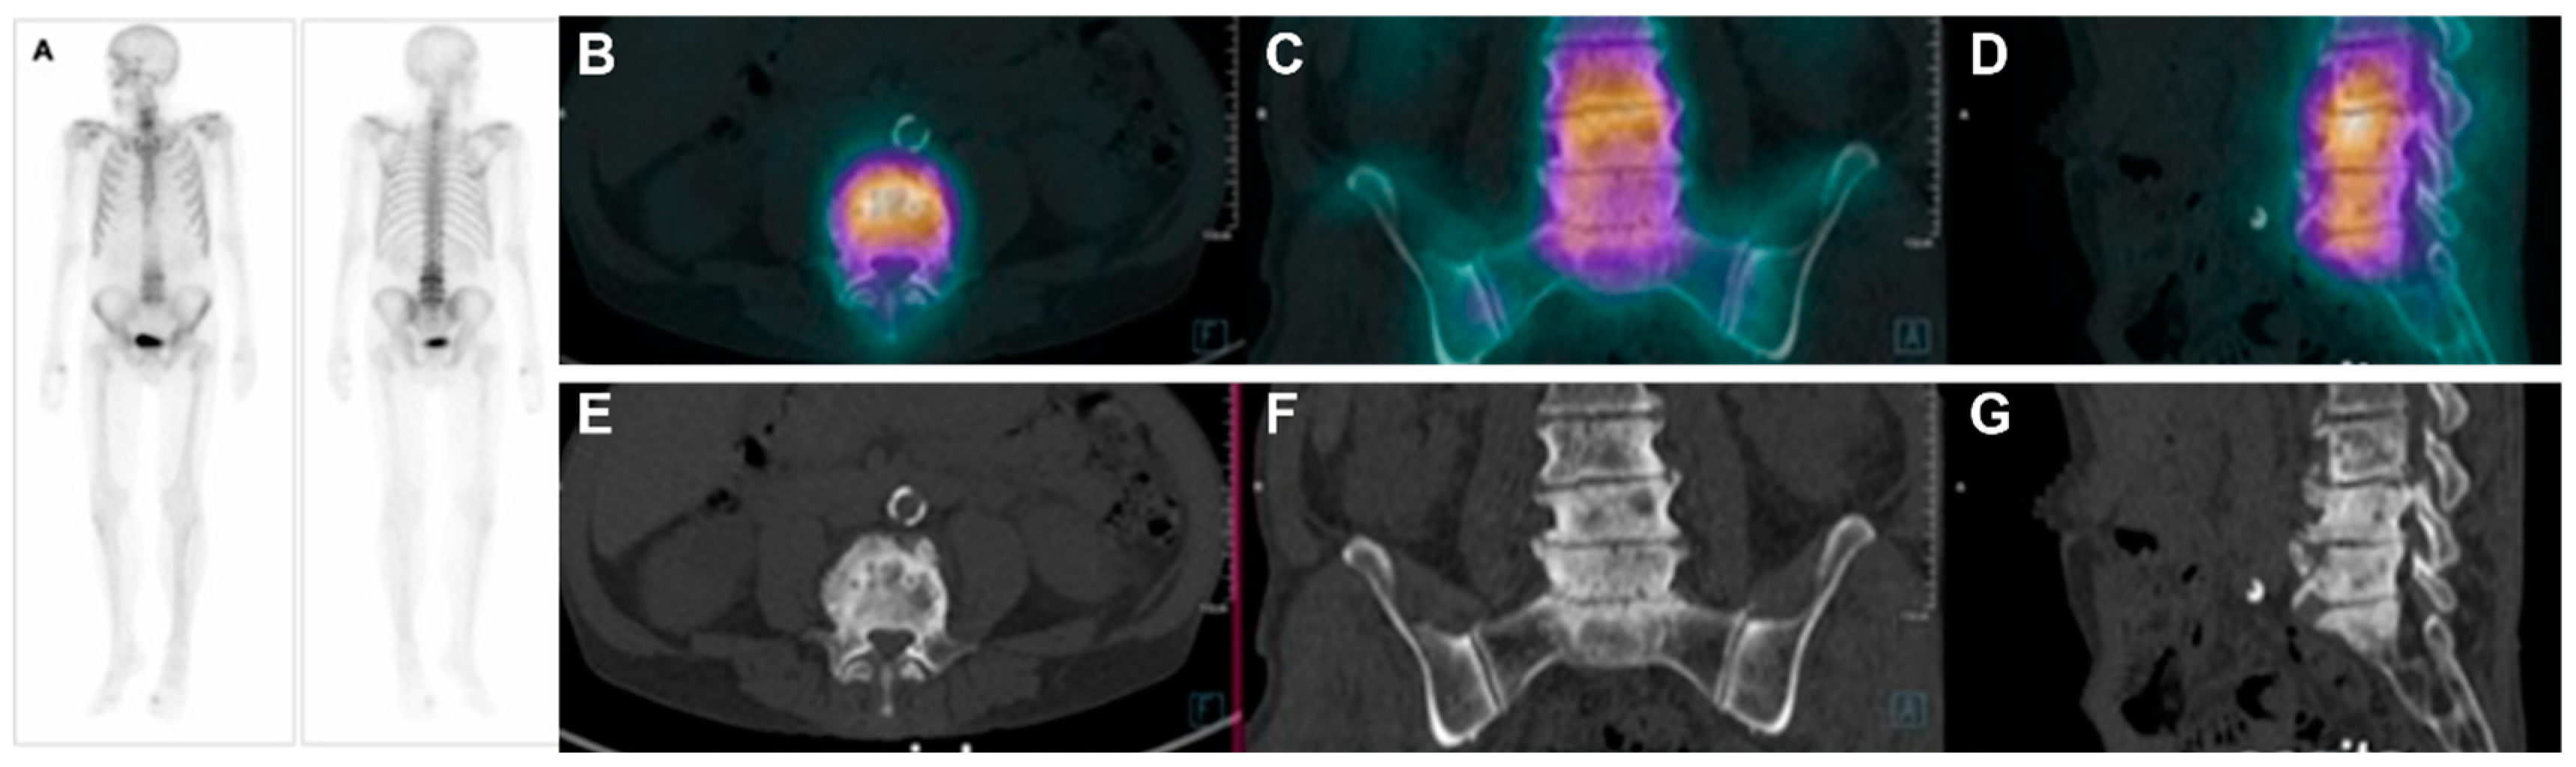

3.1. Diagnosis with Bone Scintigraphy (SPECT/CT) with 99mTc-MDP

3.2. Diagnosis with PET/CT with 18F-Fluoride